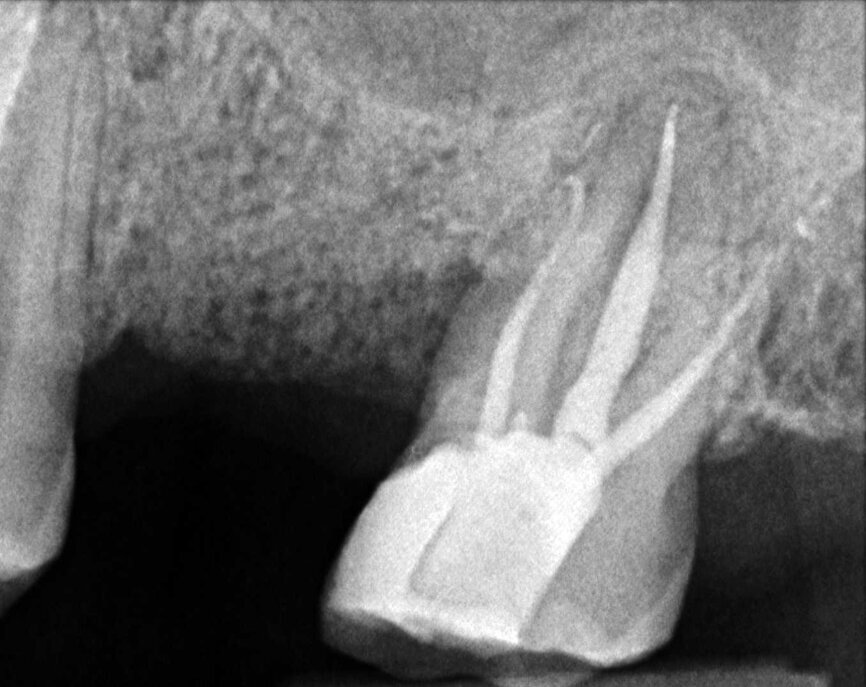

Le cas avec lequel je souhaite commencer mon exposé clinique est un exemple parfait de la difficulté à définir l’origine des symptômes d’un patient, par l’examen d’une simple radiographie intraorale. Non seulement l’examen 2D ne permet pas d’établir avec certitude la présence d’une lésion, mais surtout, il est impossible d’en déterminer la taille, la morphologie et le type. Au contraire, une analyse de l’imagerie 3D offre une image claire de la situation clinique. Chez ce patient, les coupes coronales et sagittales révèlent la présence d’une importante lésion s’étendant de l’apex de la racine mésiale de cette molaire jusqu’à la zone de furcation, tandis que les coupes axiales nous permettent d’analyser précisément l’anatomie endodontique et, en particulier, la forme de la racine mésiale, qui apparaît fusionnée avec la racine palatine. Un panorama complet du cas peut donc guider le processus de décision et orienter le plan de traitement vers une modalité bien précise de traitement (Figs. 1–4).